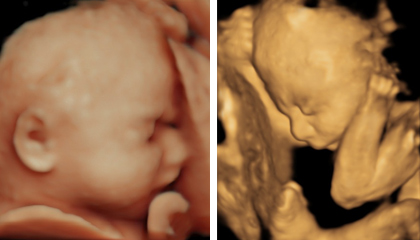

お腹の中の元気な赤ちゃんと

バーチャル対面

4D

• 妊娠20週以降の妊婦検診では、胎児計測後に4D画像の猫出を行っています

• USBをお持ちいただければ、映像を保存してお持ち帰りいただけます